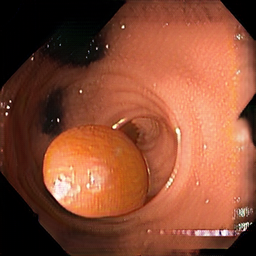

Domain adaptation

DA Synthetic

DA Real

Enric Moreu et al. “Self-Supervised and Semi-Supervised Polyp Segmentation using Synthetic Data”. International Joint Conference on Neural Networks (IJCNN) 2023.